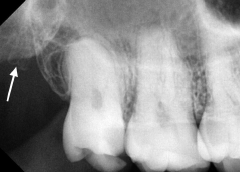

28. What is showing by arrow?

29. What is shown by the arrow?